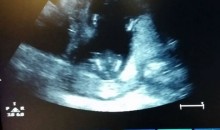

Una ecografia descobreix un bebè picant de mans dins l’úter

Si us pensàveu que ho havíeu vist tot en ecografies, anàveu ben equivocats… Durant una ecografia feta a la setmana 14, aquests pares van descobrir que el bebè, que estava dins la panxa, portava el ritme de la cançó ‘If